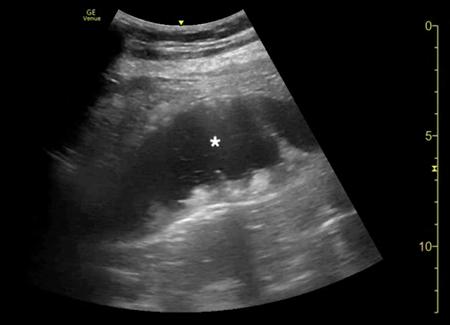

腹部床旁超声检查(POCUS)显示,胃部扩张并充满液体,高度疑似梗阻(图1,2)。

(图1 POCUS检查显示胃部膨胀充满液体[星号])

当怀疑有胃扭转时,选择初始的影像学检查非常重要,因为诊断延迟可能导致致命的并发症。CT检查高度可靠,主要有两种表现,即正常的胃窦幽门移行区和胃窦位置异常,诊断急性胃扭转的敏感性和特异性均为100%。POCUS是一种有效的非侵入性影像检查方式,主要用于床旁评估。此外,POCUS无辐射,并可根据临床情况随时进行重复检查。本例患者POCUS检查显示,胃部严重扩张,胃内容物分层,类似胃出口梗阻(GOO)的“黑白饼干”征象。POCUS还可以用来动态观察胃减压成功与否。